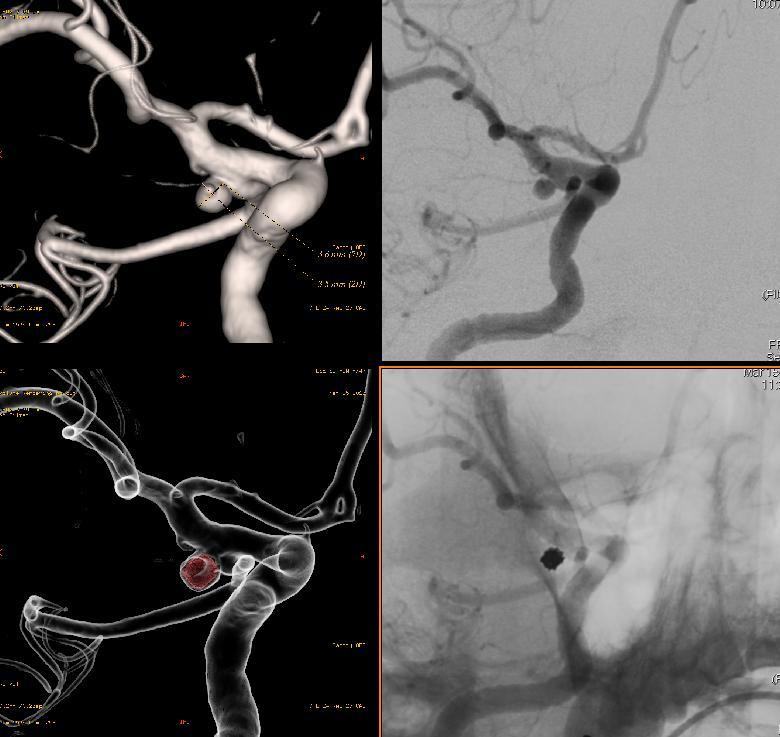

먼저 마취가 시작되고 권배주 교수님은 뇌혈관조영술을 통해 뇌동맥류의 정확한 위치와 크기, 주변 혈관과의 관계 등등을 면밀히 살피신 후 코일색전술을 준비하십니다.

미세도관을 이용하여 파열된 뇌동맥류에 안전하고 정확하게 초선택 하신 후 프레임을 감을 수 있는 코일을 선택하시어 뇌동맥류만 완전히 감사면서 정성 혈관쪽으로는 내려오지 않도록 감으시고 나머지 빈 공간에는 여러개의 채우는 코일을 이용하여 순차적으로 채우기 시작하십니다.

여러개의 코일이 채워지고 더이상 빈 공간이 보이지 않아 뇌혈관조영술로 확인한 결과 뇌동맥류는 보이지 않고 그곳에 코일로 가득 채워져 있어 더이상 뇌동맥류쪽으로 혈류가 흐르지 않는 것을 확인하시고 시술을 종료하십니다